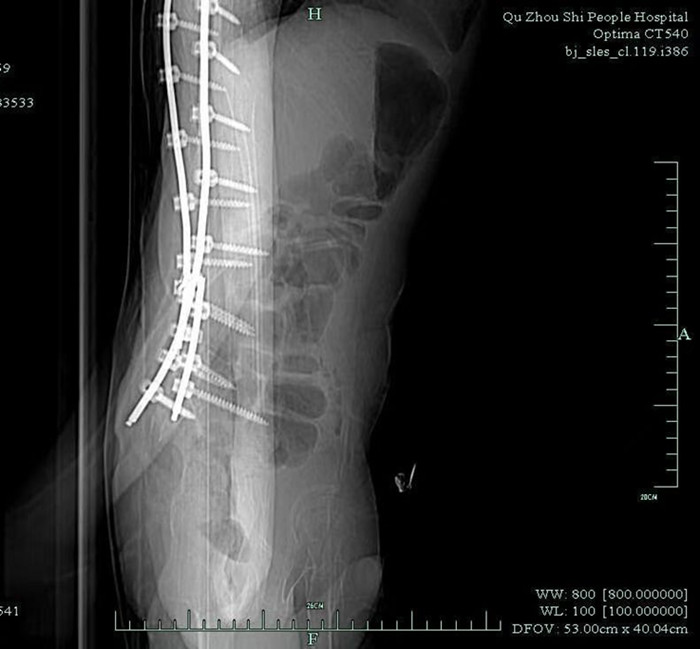

早就收過病危通知書的小徐,由于沒有肌肉力量的支撐,大部分骨骼被擠壓變形。體重不足40公斤的他,幾年前因?yàn)榧怪鶄?cè)彎,靠著打進(jìn)身體里的37枚鋼釘,才勉強(qiáng)能在輪椅上坐穩(wěn)。

鞘內(nèi)注射是神經(jīng)內(nèi)科醫(yī)生的基本操作,本身并沒有多大難度。但由于小徐長年疾病導(dǎo)致脊椎側(cè)彎,椎管變得彎彎曲曲,還有37根鋼釘橫亙其中,這讓原本并不復(fù)雜的注射治療變得十分困難。